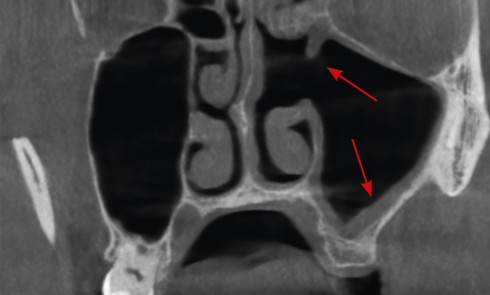

Contexte clinique Un patient de 30 ans est adressé pour extraction de la 28 incluse en raison de l’apparition de...